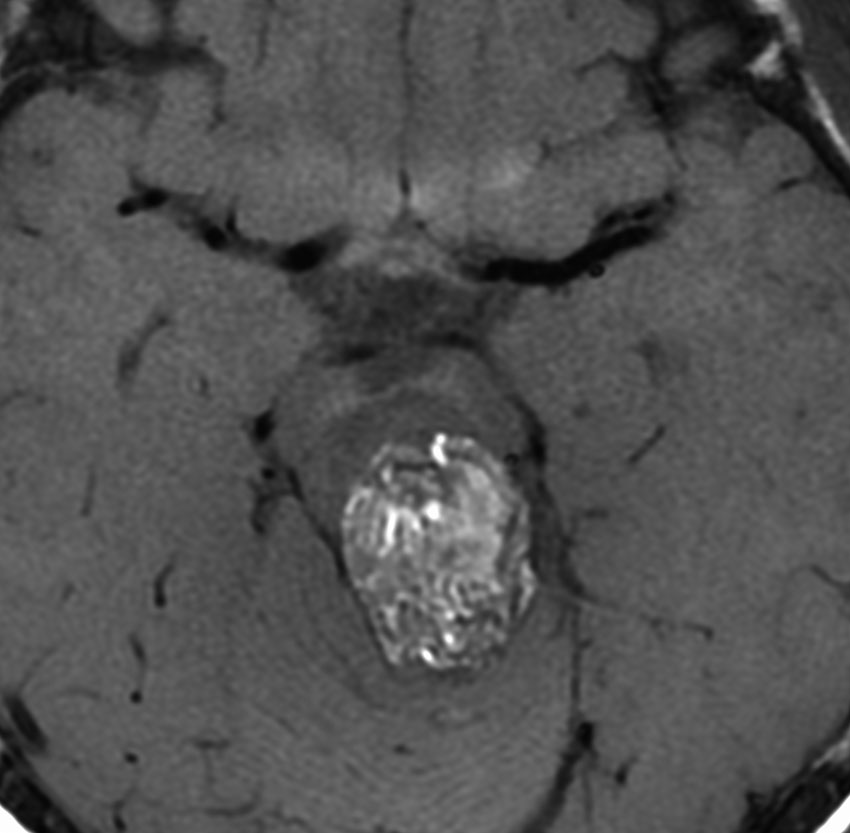

9歳男児の松果体奇形腫です。生検術と第3脳室開窓術を受けましたが,摘出術のリスクが高すぎるということで化学療法を6コース。2年間経過観察されましたが,腫瘍が増大しました。私のところへ来た時には,前後径73mmありました。

左からT2, swan, T1です。これが 類皮のう胞 dermoid cyst ということがわかります。類皮のう胞単独,あるいは成熟奇形腫の大部分としての類表皮のう胞は,かなり頻度の高いものです。松果体腫瘍で奇形腫を疑ったらまず,類皮のう胞の混在を疑います。それがあれば,かなりの確率で成熟奇形腫 mature teratomaです。

類皮のう胞は内部がほとんど皮脂,ケラチン,汗,毛髪なので,簡単に砕けるし,掻き出し吸い取ることができます。松果体成熟奇形腫の中では最も戦いやすい相手と言えるでしょう。再発しないようにするには,周囲ののう胞壁(真の腫瘍細胞)を完全摘出するしかありません。放射線も化学療法も何も効かないし,のこせば必ず再発します。

右迂回槽にちょっとdebrisは残っていますが完全摘出できました。病理は他の成分を少し混じる成熟奇形腫です。術後3年間再発はありませんし,学校へ通って体育もできています。

この手術はもちろん簡単ではありません,でもほとんどが類皮のう胞であるということがわかったので踏み込めたのです。